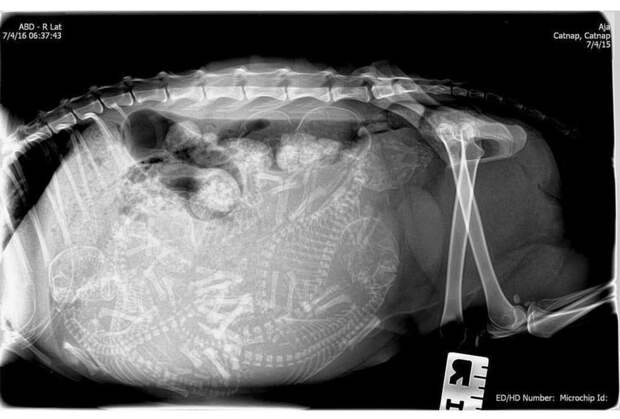

3. Беременная кошка

4. Ещё одна кошка